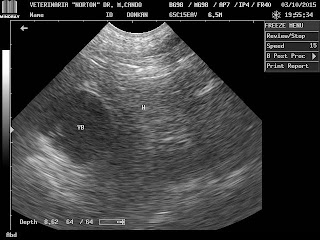

CIRUGÍA GENERAL Y DE TEJIDOS BLANDOS, TRAUMATOLOGÍA Y ORTOPEDIA, CARDIOLOGÍA, RAYOS X, ECOGRAFÍAS, LABORATORIO CLÍNICO....DR. MARCELO E. CANDO L. M.V.Z. -ESTAMOS UBICADOS AL SUR DE QUITO EN LAS CALLES HOPPE NORTON S-928 Y ADRIÀN NAVARRO, A UNA CUADRA DEL PATRONATO MUNICIPAL SAN JOSÈ. INFORMES AL 02-2648 115 -0984992384